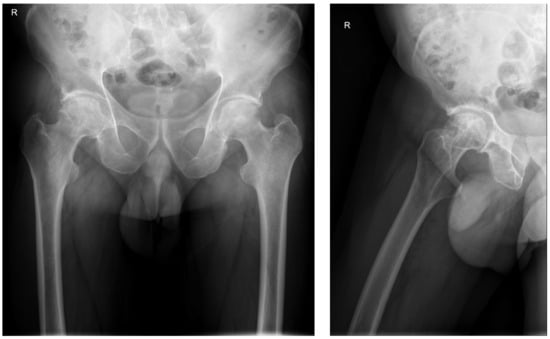

The initial radiography of the right hip joint showed a slight narrowing of the joint space and destruction of the femoral head (Figure 1).

Figure 1. X-ray of the right hip on admission.